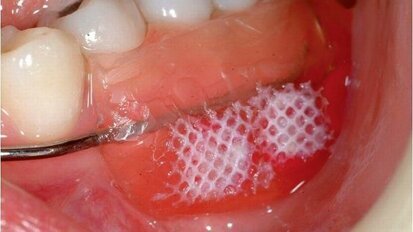

Weefsel van runderhart geschikt bij teruggetrokken tandvlees

LONDEN – Collageen van runderharten kan worden getransplanteerd op teruggetrokken tandvlees. Een team van Duitse en Zwitserse onderzoekers heeft ...